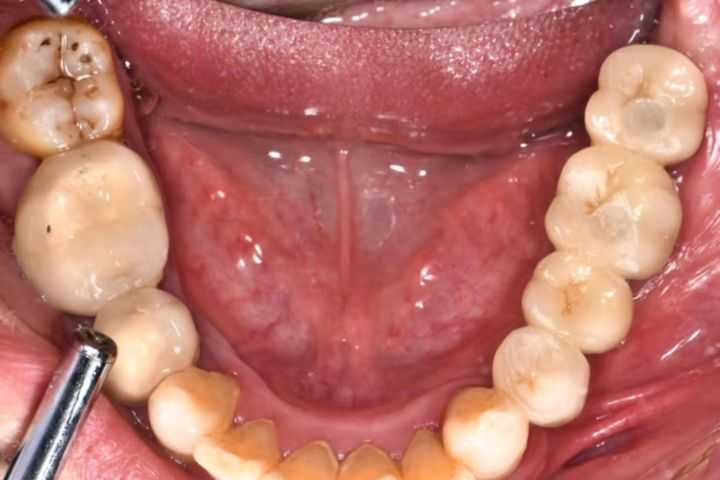

下面這組案例,種植牙修復(fù)冠破損,拆卸后,頸部有一片粘接劑。

激光筆照射后,發(fā)出粉色熒光,這說(shuō)明有細(xì)菌感染。粘接劑殘留,是一個(gè)嚴(yán)重的菌斑滯留因素。一般的種植醫(yī)生不懂修復(fù),可能會(huì)出現(xiàn)這種問(wèn)題。

可以用口內(nèi)粘結(jié)代型法降低風(fēng)險(xiǎn),或者口外粘接。